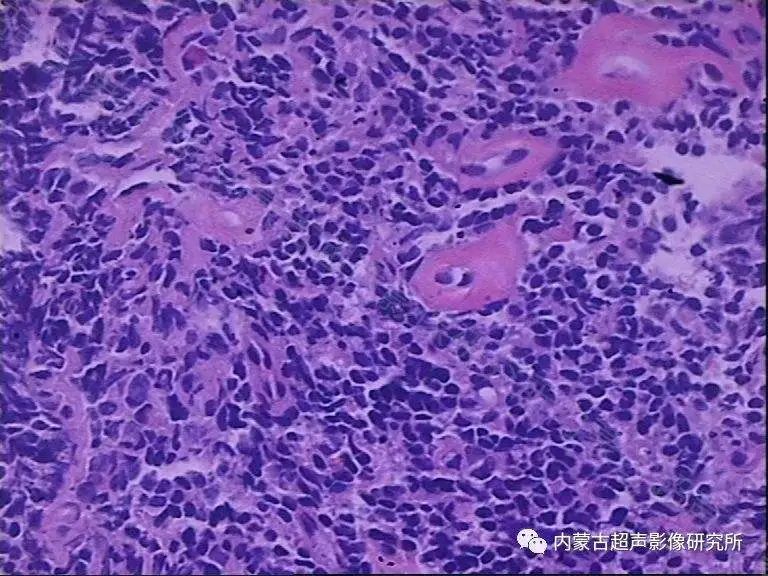

高度侵袭性淋巴瘤

高度侵袭性淋巴瘤包括伯基特淋巴瘤、前驱B/T淋巴母细胞性淋巴瘤及NK/T细胞淋巴瘤。CHOP方案对此型淋巴瘤效果欠佳,故对于此型淋巴瘤CHOP方案并不是其一线化疗方案。对于低危的伯基特淋巴瘤,指南推荐的联合化疗方案为CODOX-M IVAC交替方案及HyperCVAD方案(高剂量CHOP联合高剂量甲氨蝶呤及阿糖胞苷),同时联合利妥昔单抗。淋巴母细胞性淋巴瘤患者的治疗则推荐选用ALL方案,如HyperCVAD方案、BFM90方案,CALGB方案,阿糖胞苷联合大剂量米托蒽醌等。对于T细胞淋巴瘤,各种方案效果欠佳,推荐使用强烈化疗,如CHOP、EPOCH、HyperCVAD/ MTX-Ara-C方案,二线治疗方案包括有DHAP、ESHAP、ICE、 MINE(异环磷酰胺、米托蒽醌、依托泊苷)等方案。二线治疗中也可选择部分姑息性治疗方案如GDP等。在以上化疗方案使用过程中,应注意水化、碱化,防止肾衰竭的发生。